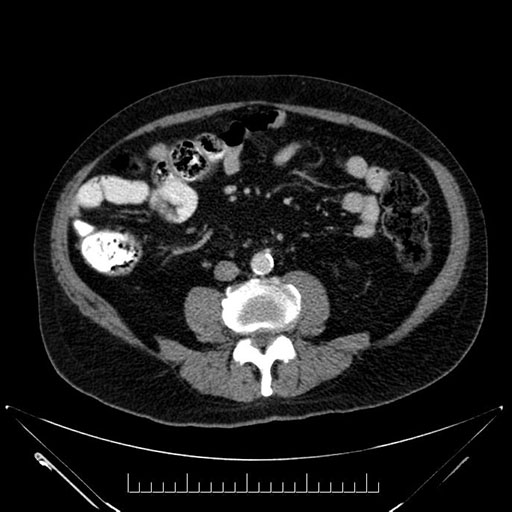

Imaging Analysis

Look through the patient's CT scan to identify any areas of concern for the necessary procedure.

Based on your CT findings, which issue(s) would give reason for "planned slowing down moment(s)" in this case?